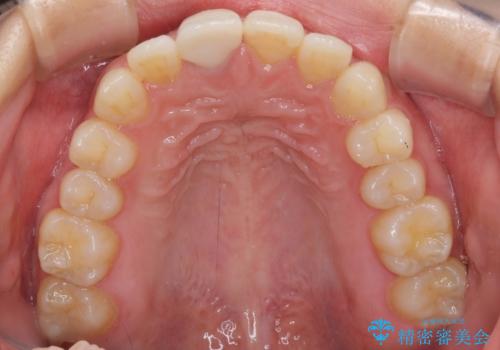

- 近医にて被せた前歯のクラウンの色の違いを気にして来院された患者様です。

オーダーメイドのオールセラミッククラウンにて補綴することとしました。

元々すきっ歯であったため、隙間を全て埋めると左右で大きさがアンバランスとなることが懸念されました。

違和感のない程度に隙間を小さくして、自然な見た目に仕上げました。